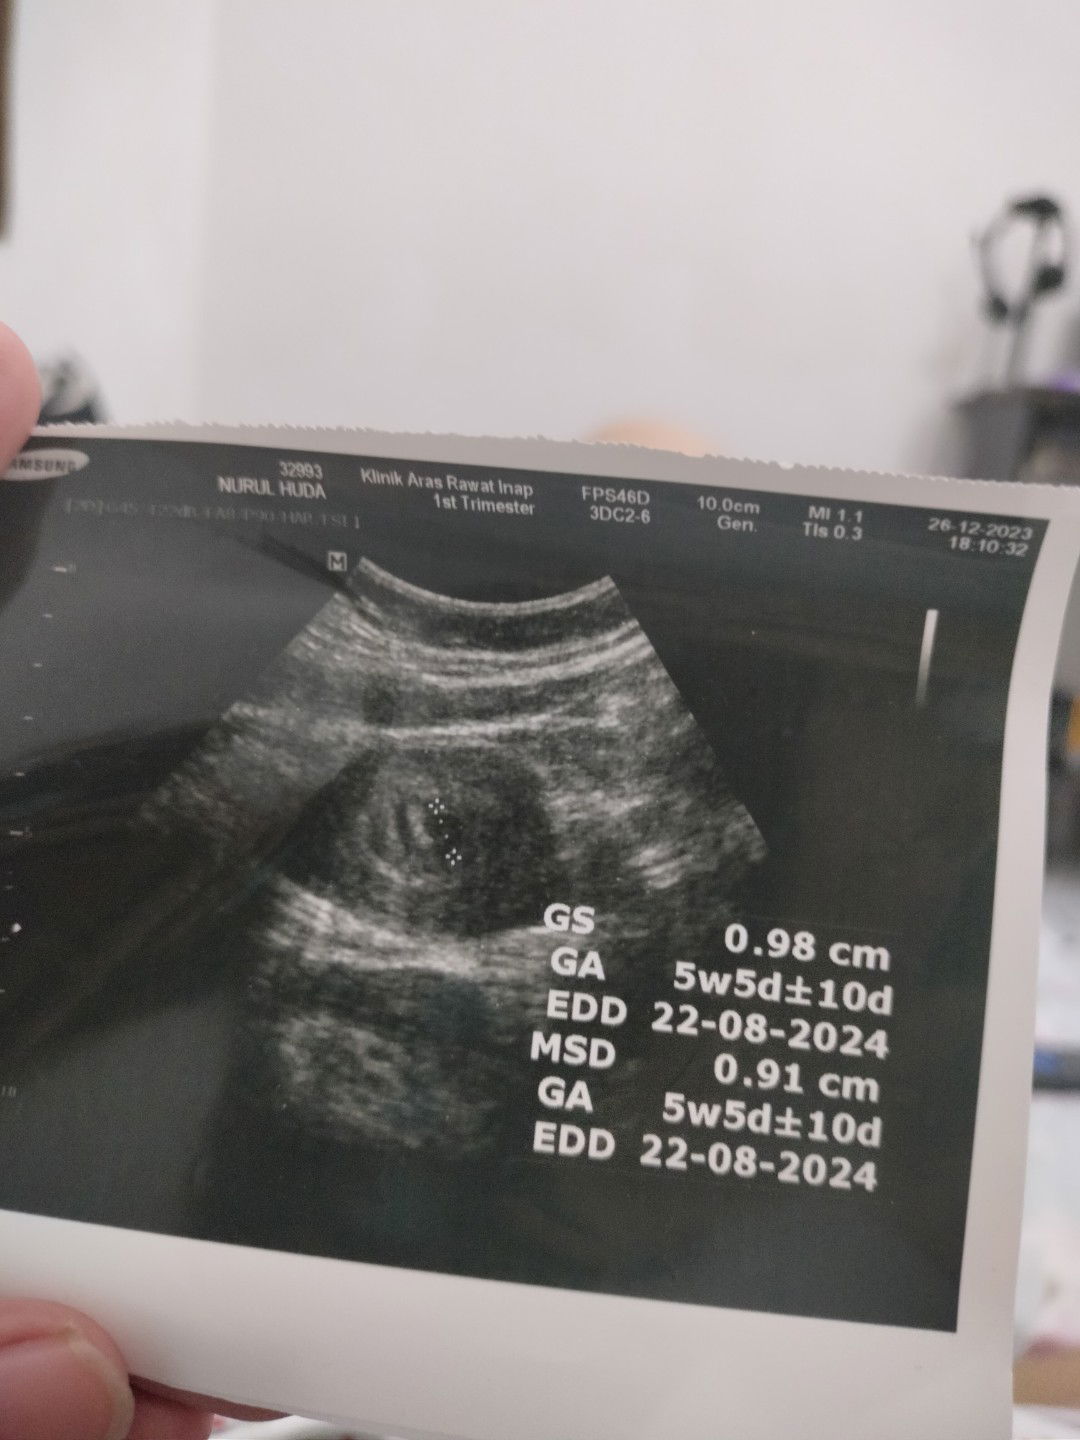

seminggu yang lalu saya nge flek bun uk 5w. usg ke bidan baru keliatan kantung aja, jadi disuruh usg 2 minggu lagi. dikasih obat penguat dan disuruh bedrest. hari ke-3 flek makin banyak, saya langsung ke igd. dokter spog juga bilang cek 2 minggu lagi karna uk masih kecil. sempat dirawat semalam, diresepkan obat penguat yg lebih bagus dan bedrest. alhamdulillah udah 2 hari ini gak keluar flek.